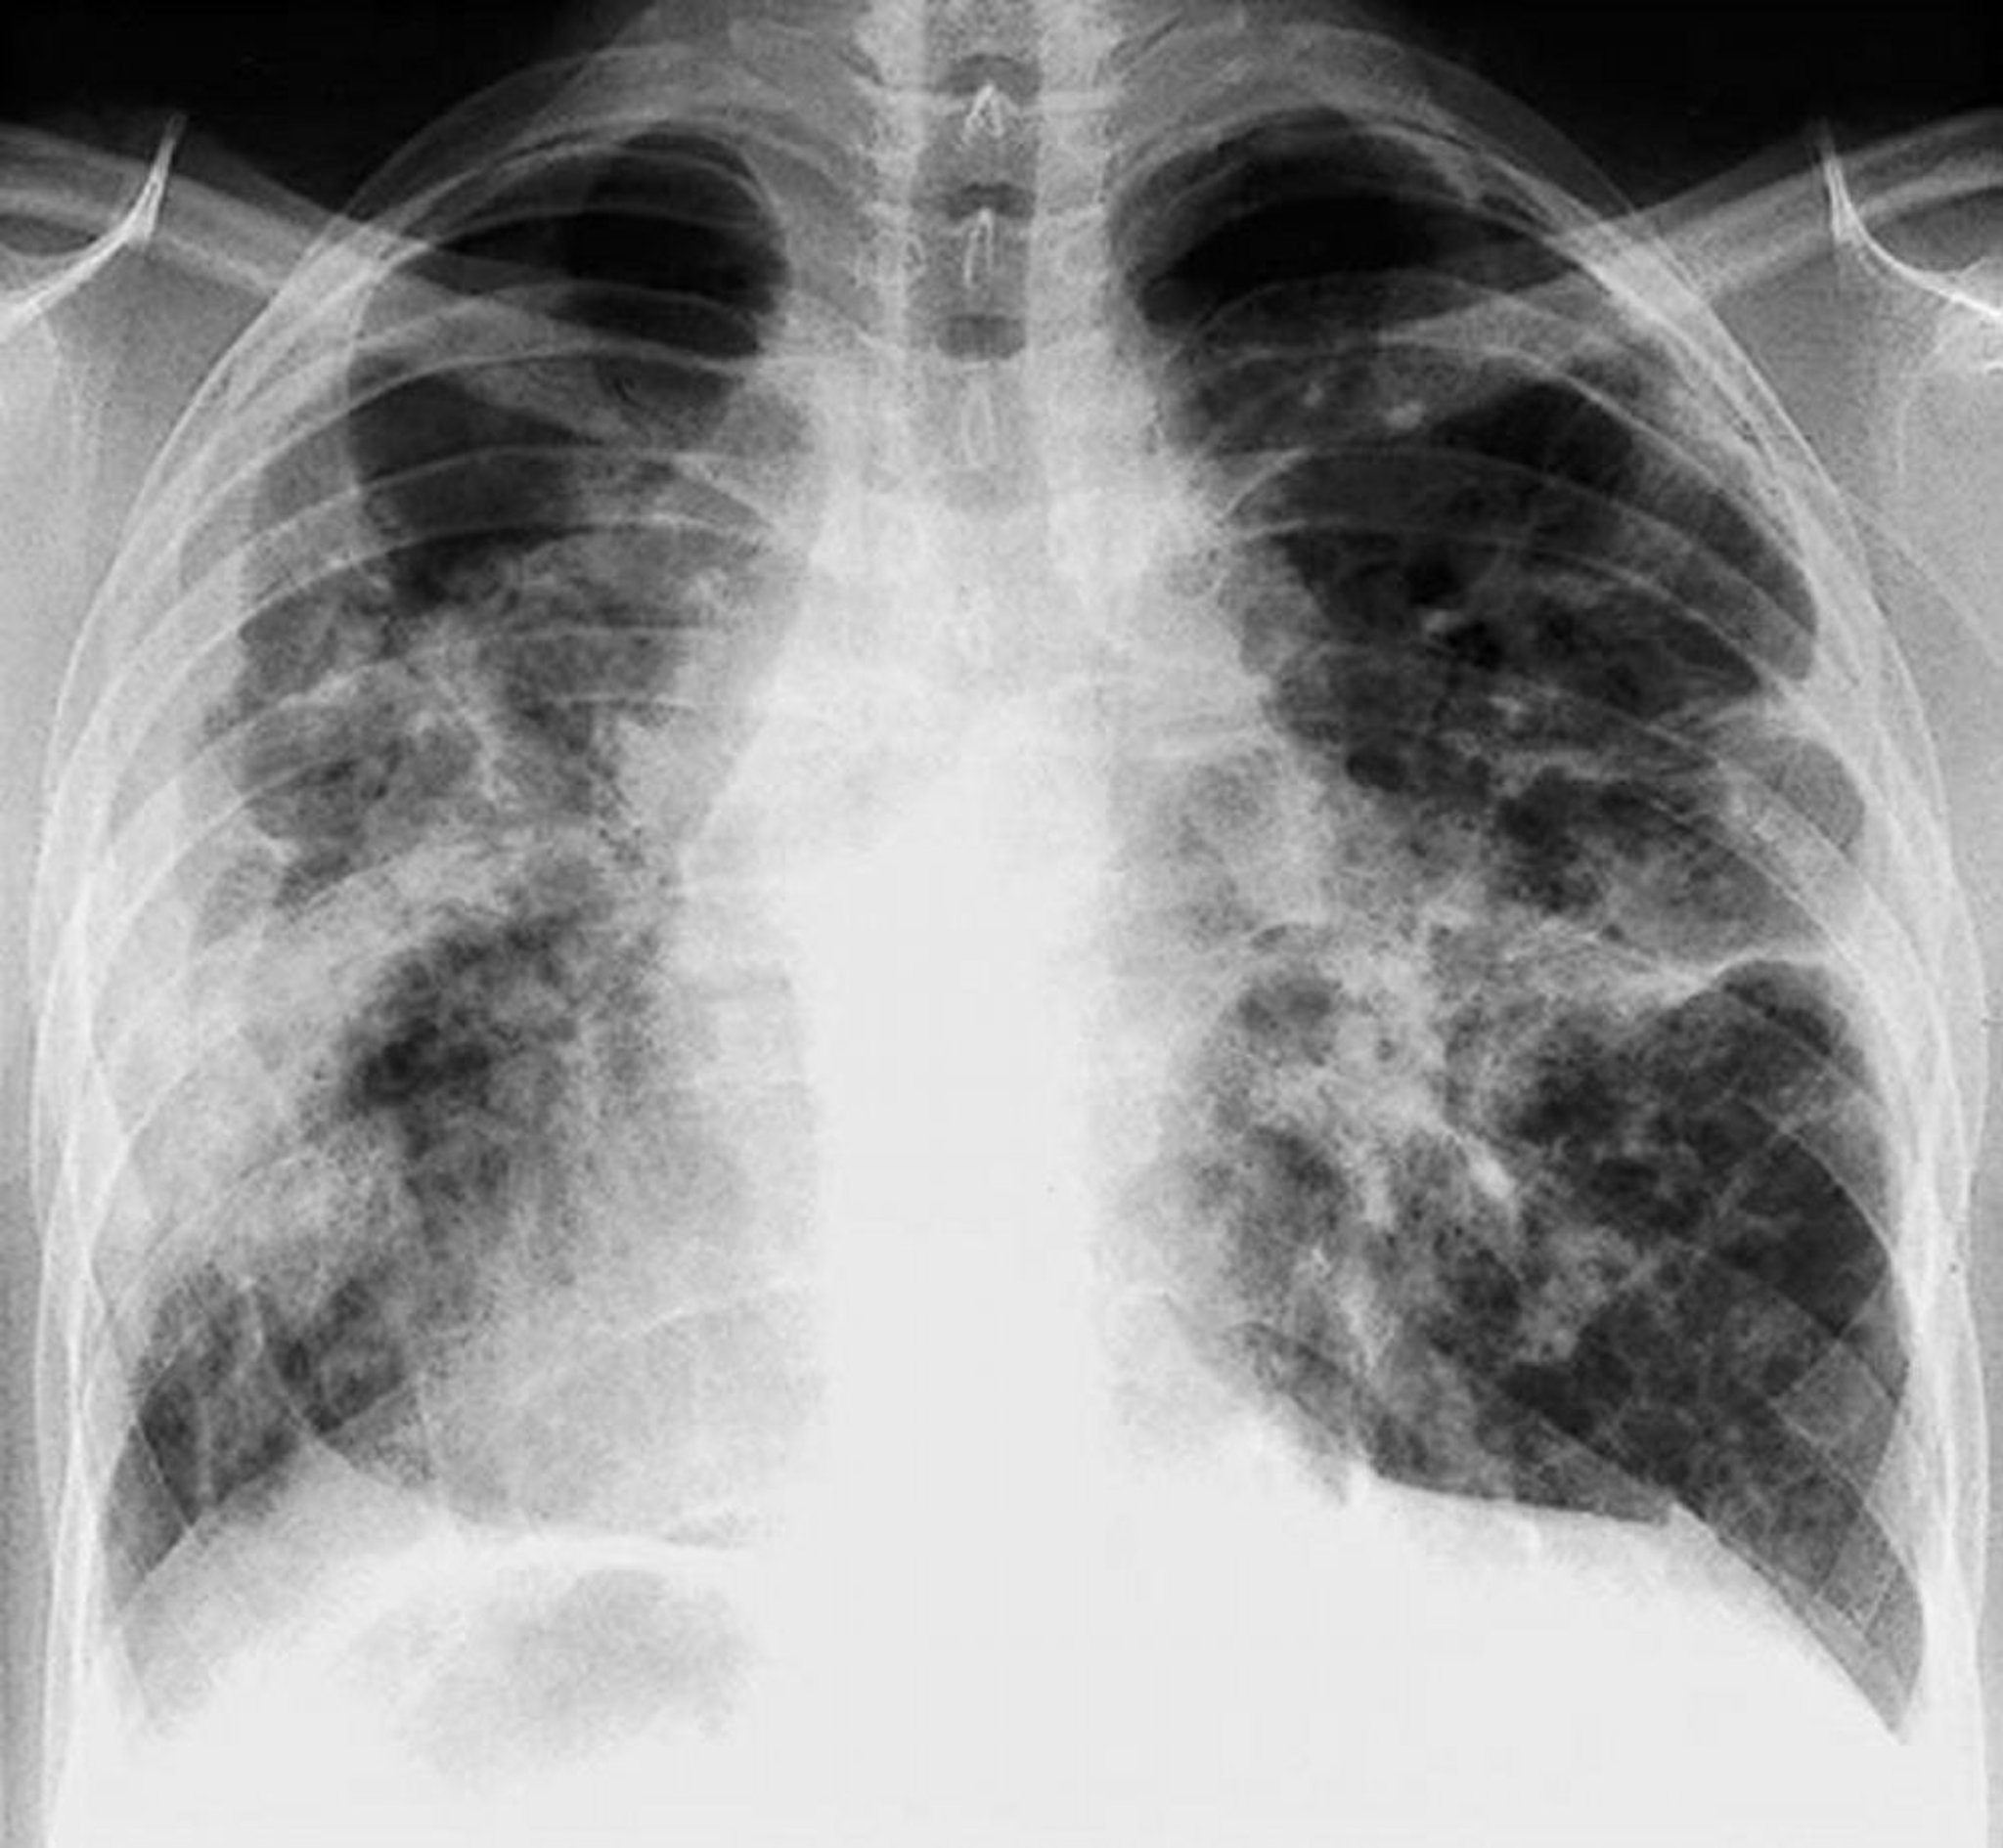

Sarcoidosi (stadio IV)

Grave fibrosi diffusa con adenopatia ilare e alterazioni cistiche dei lobi superiori nella sarcoidosi allo stadio IV.

By permission of the publisher. From: Tanoue L, Elias J. In Bone's Atlas of Pulmonary and Critical Care Medicine. Edited by J Crapo. Philadelphia, Current Medicine, 2005.